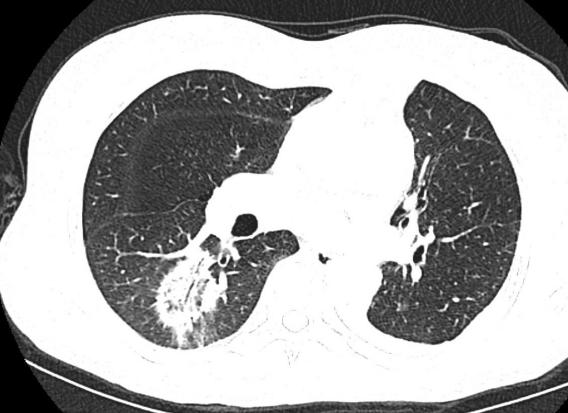

术前

患者张某,65岁,老年女性,于2022年2月份查体发现双肺占位,左肺上叶软组织密度灶(直径约4cm)、右肺磨玻璃结节灶(GGO,直径约3cm),针对左肺占位行CT引导下穿刺活检,病理提示肺腺癌,经我院MDT多学科专家会诊讨论,为该患者制定了序贯式治疗方案:1、左肺肿瘤实行外科手术切除;2、右肺病变实行经皮穿刺微波消融术。患者于2022年2月份在胸外科全麻下行胸腔镜下左肺上叶切除+纵隔淋巴结清扫术,术后恢复顺利,回家休养。